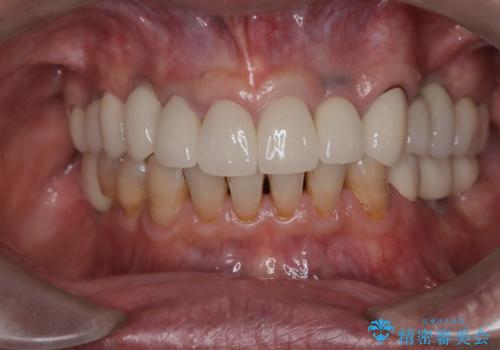

- 「被せ物が揺れている」を主訴に来院された患者様です。診査診断を行い被せ物が外れているのではなく、コアという土台ごと外れていたので、土台ごとやり変えた後オールセラミッククラウンで治療を行いました。

ファイバーコアという土台を建てるときに唾液が入ると接着に良くないのでラバーダムシートを使用しています。加えてマイクロスコープを使用しながら行う事で外れにくい土台を作ることが出来ます。その後、形成を行いシリコンで型取りしたのち、オールセラミッククラウンで修復しました。